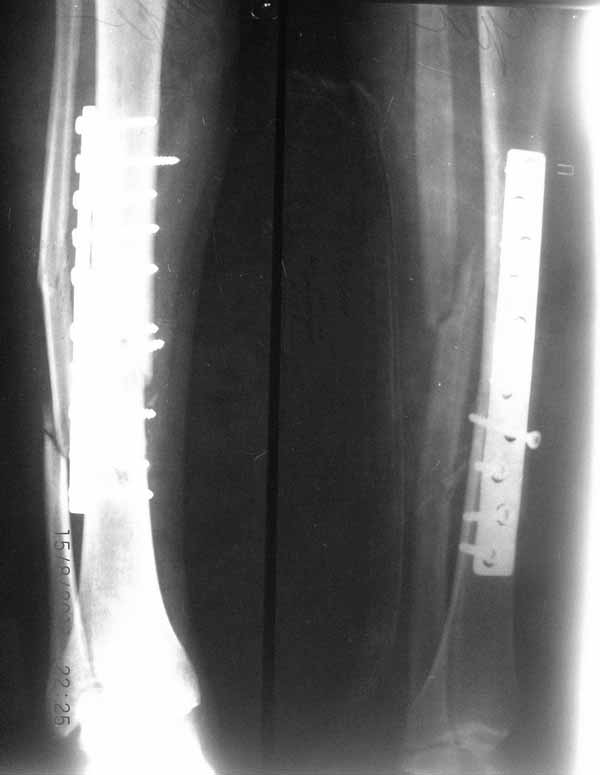

Первично у пациента травма в марте 2009г, когда в результате ДТП получил открытый оскольчатый перелом обеих костей правой голени на границе средней и нижней трети. При поступлении - скелетное вытяжение, затем по заживлению раны произведен остеосинтез пластиной. Со временем (точное время сказать затрудняется) пациенту разрешили полную нагрузку на конечность. Через год после операции пластина сломалась, в связи с чем пластина удалена и установлен интрамедуллярный гвоздь. Через 2 месяца разрешили полную нагрузку и гвоздь сломался. В сентябре 2010 произведено наложение спицевого компрессионно-дистракционного аппарата. В мае 2011 появилось отделяемое в местах проведения спиц, в связи с чем аппарат демонтирован. Правая голень временно иммобилизирована гипсовой повязкой, разрешена нагрузка на правую нижнюю конечность. После снятия повязки - клиника ложного сустава обеих костей правой голени. В настоящее время отмечается угловая деформация правой голени на границе средней и нижней трети с отклонением оси в медиальную сторону. Кожные покровы изменены за счет трофических нарушений(имеют более темную окраску по сравнению со здоровой ногой)На коже рубцы на месте проведения спиц.Движения в коленном и голеностопном суставах в полном объеме безболезненны. Пульсация артерий на стопе отчетливая, выпадение чувствительности от третьего луча в латеральную сторону по тылу стопы. В таком виде пациент оказался у нас. Рады выслушать предложения о тактике лечения.